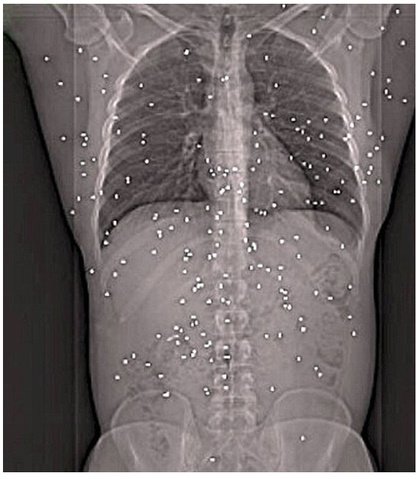

총탄 파편 150발 맞고도 살아난 남자

25회 총탄 파편 150발 맞고도 살아난 남자

저건 살아도 좋은게아님 저 파편은 전부제거가 어렵기때문에 점점 납중독으로 단명하게됨..진짜 안됐다..ㅠㅠ